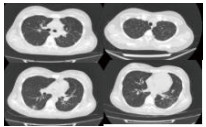

入院相关化验结果,血常规:WBC 0.8 g/L, NE 0.5 g/L, HGB 126.0 g/L, PLT 47.0/L;血气分析:pH 7.450,PaCO2 32.90 mmHg,PaO2 52.50 mmHg,SaO2 89.3%, LAC 3.9 mmol/L, HCO3- 22.5 mmol/L;心肌标志物:CK 4 668 U/L,MB 46.2 ng/mL,cTnI 0.52 ng/mL,MyO 1 884 ng/mL;肾功能:UREA 7.10 mmol/L,CREA 80.7 μmol/L,Glu 8.35 mmol/L,Na+ 131 mmol/L,K+ 3.9 mmol/L;肝功能:ALT 47 U/L,AST 211 U/L,ALB 22.4 g/L,TBIL32.93 μmol/L,DBIL 19.01 μmol/L; D-Dimer 18 893 μg/mL;BNP 986 pg/mL;ESR 66 mm/h;CRP 320 mg/L; 降钙素原53.8 ng/mL。腹部B超(-);子宫附件B超(-);超声心动图(-)、入院前胸部CT平扫提示双肺多发片状、团块病灶,见图 1。

| 图 1 入院前胸部CT |

2.4 影像学除外肺部转移瘤的原因分析患者住院时高热,喘憋比较明显,影像学提示双肺弥漫性浸润病灶(图 1)。最初考虑可能为多发肺部转移瘤?随着治疗的好转以及影像学的演变,最终排除了肺部转移瘤的诊断。